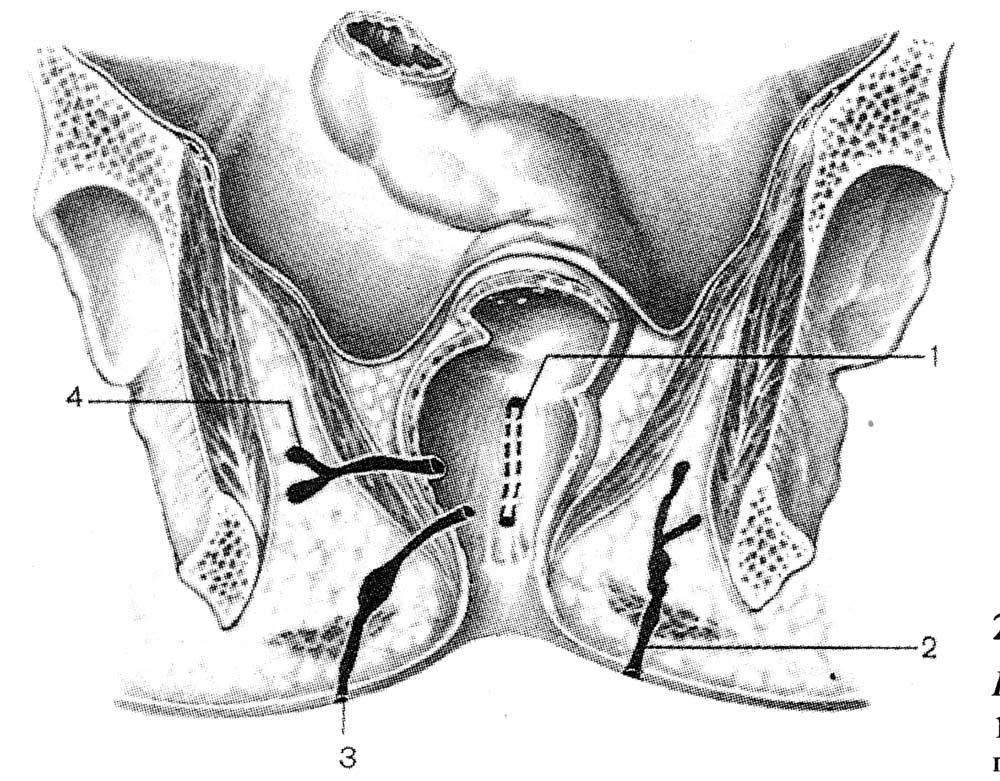

Пластика влагалища, совмещенная со слинговой операцией, предназначена не только для коррекции размеров влагалища, но и для лечения стрессового недержания мочи.

ОСОБЕННОСТИ ОПЕРАЦИИ И ПОСЛЕОПЕРАЦОННЫЙ ПЕРИОД

Пластика передней и задней стенок влагалища с одномоментной установка сетчатого импланта (слинг-системы) позволяет избавиться от перечисленных тревожных симптомов, восстановить положение матки, уретры, мочевого пузыря и укрепить мышцы тазового дна. Имплант обладает 100% биосовместимостью с тканями человеческого организма.

Операция проводится под наркозом и длится от 30 до 60 минут. В снятии швов нет необходимости благодаря специальному рассасывающемуся материалу, который применяют наши хирурги при их формировании.

Вагинопластика предназначена для хирургического сужения влагалищного канала и включает удаление избыточной слизистой оболочки влагалища из сводов влагалища.Он может включать переднюю кольпорафию, заднюю кольпорафию, иссечение латеральной слизистой оболочки влагалища или различные комбинации этих хирургических методов (рис.). Некоторые хирурги также проводят пластику леватора по средней линии, чего, по нашему мнению, лучше всего избегать, так как это может вызвать выраженную диспареунию.

Вагинопластика предназначена для хирургического сужения влагалищного канала и включает удаление избыточной слизистой оболочки влагалища из сводов влагалища.Он может включать переднюю кольпорафию, заднюю кольпорафию, иссечение латеральной слизистой оболочки влагалища или различные комбинации этих хирургических методов (рис.). Некоторые хирурги также проводят пластику леватора по средней линии, чего, по нашему мнению, лучше всего избегать, так как это может вызвать выраженную диспареунию.